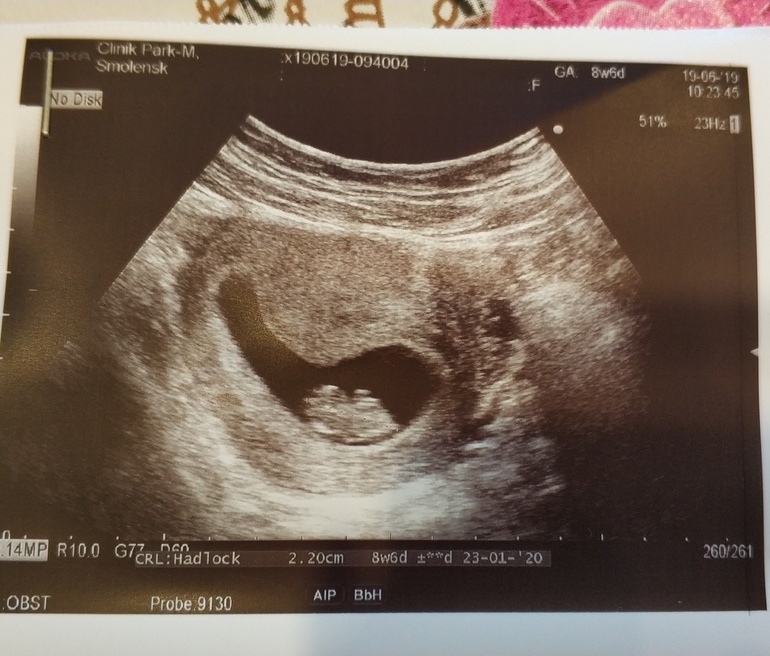

Вот мы какие!😘

Клааааас какой малышастик уже Вот мы

У нас с вами одинаковый срок у меня 19 тоже 8+6) и тоже 22мм. Меня на скрининг ещё не записали, жду звонка врача, назвала КТР они сами рассчитывают когда надо на скрининг. Слышала что 20 недель важнее скирининг и расслабится все равно вряд ли получится. Но очень хочется!